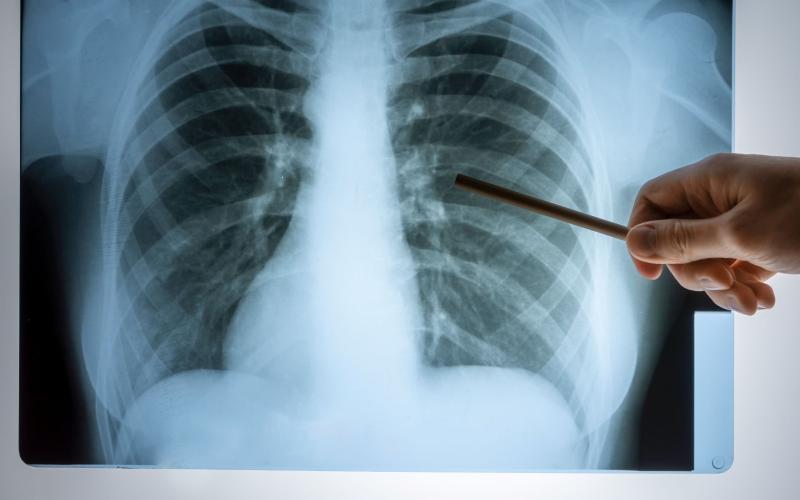

La neumonía es una infección que afecta los pulmones y puede causar complicaciones graves si no se atiende a tiempo. Esta enfermedad puede ser causada por diferentes tipos de bacterias, virus y hongos, por lo que es fundamental conocer cómo prevenirla y manejarla correctamente.